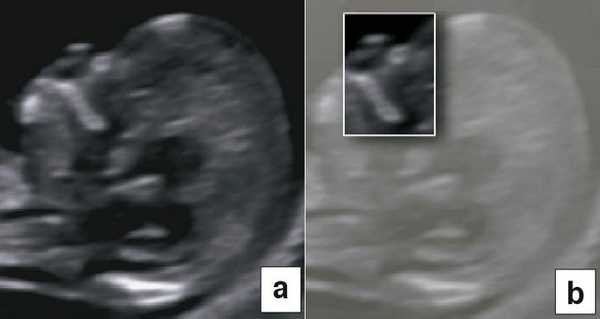

В начале 90-х годов прошлого века в практику был внедрен метод измерения толщины воротникового пространства (ТВП) в I триместре беременности, и к настоящему времени его считают показателем не только анеуплоидии, но и широкого спектра наследственных синдромов и пороков развития [2]. K. Николаидес (K. Nicolaides) с группой исследователей предложили новую модель скрининга на анеуплоидию и установили правила использования этого метода, в частности необходимость применения кривой обучения, проведения аудита, качественного (процедура оценки качества изображений) и количественного (медиана, дельты-ТВП и т.д.). Фонд медицины плода (Fetal Medicine Foundation) стандартизировал предложенный ими клинический протокол и установил правила сертификации для повышения качества медицинской помощи и уменьшения изменчивости результатов данных скрининга [3, 4]. Измерение ТВП можно проводить вручную (рис. 2a) или полуавтоматически (рис. 2b), чтобы результаты измерений были более воспроизводимыми. Кроме того, компания Samsung разработала дополнительный метод измерения показателей ТВП - 5D NT, позволяющий точно выявить срединно-сагиттальную плоскость и улучшить оценки по шкале Германа (Herman score).

В 90% случаев крупные анеуплоидии у плодов можно обнаружить с помощью комбинированной оценки возраста матери, измерений ТВП и сывороточных маркеров у матери (РАРР-А и свободный бета-ХГЧ) [8]. Результат такого скрининга можно улучшить, исследуя сывороточные маркеры раньше, на сроках от 9 до 10 нед, и проводя УЗИ на 12-й неделе для выявления дополнительных маркеров, таких как носовая кость плода, кровоток в венозном протоке и через трехстворчатый клапан (рис. 5) [9]. Кроме того, выявлять часто встречающиеся хромосомные аномалии у плода позволяет неинвазивное пренатальное тестирование (Non Invasive Prenatal Testing - NIPT).

Рис. 5. Оценка анеуплоидии по ультразвуковым маркерам: толщина воротникового пространства (a), носовая кость (b), венозный проток (c), кровоток через трехстворчатый клапан (d).